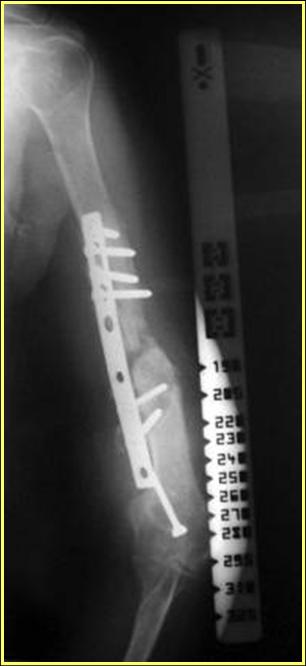

> Уважаемые коллеги! Обратилась женщина 38 лет, соматически здорова,

> ORIF наружным доступом в 2005 году (к сожалению

> снимки пока не нашли), перелом типа В1. После остеосинтеза никуда

> не обращалась. Летом прошлого года (через 2 года

> после операции) во время перетаскивания стиральной машины появились

> боли в оперированном плече, но пришла лишь

> сейчас. Клинически: варусная деформация, патологическая

> подвижность, объем движений в локтевом суставе почти полный,

> неврологических расстройств нет, признаков инфекции нет. Коллеги,

> как вы думаете, возможно ли срастить данный

> неоартроз? Микрохирургия  недоступна. Честно говоря, не встречаясь

> с такими последствиями никогда ранее, надеюсь на

> помощь "коллективного разума".

Типичная положительная ситуация для интрамедуллярного остеосинтеза с

использованием опорного металлокаркаса для компенсации дефекта.

Послеоперационное ведение активное или агрессивно-активное.  Каркасы

можно заказать в МАТИ. Успехов. ЛАФ.